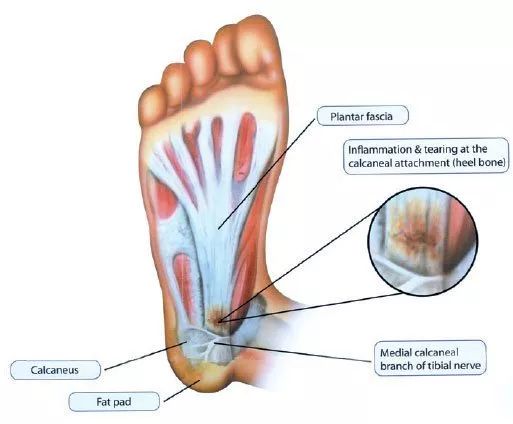

脚跟痛最常见原因之一是足底筋膜炎。大约十分之一的40-60岁的人都会经历这样的痛。 那么,什么是足底筋膜呢?足底筋膜是穿过脚底的一层厚厚的纤维结缔组织,从脚跟骨一直连接到脚趾,并且支撑着足弓。

在正常情况下,足底筋膜就像一个减震的弓弦,支撑着我们的足弓。走路时,当我们的脚着地的时候,会拉伸足底筋膜。如果拉伸的张力或压力太大,就会在筋膜上产生小的撕裂。反复拉伸和撕裂会刺激足底筋膜并引起炎症反应,形成疤痕组织,在走路和站立时就会疼痛。然而,在许多情况下,具体的引起足底筋膜炎的原因尚不清楚。